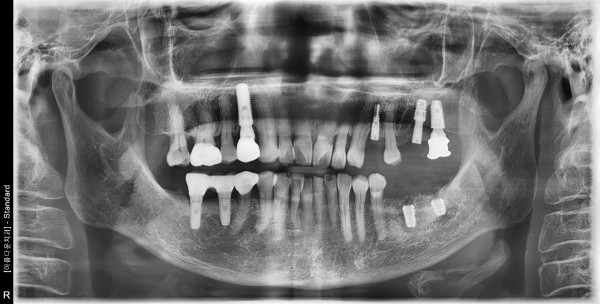

70세 여자환자 / 좌측 상하악 구치부 발치후 뼈이식및임플란트식립